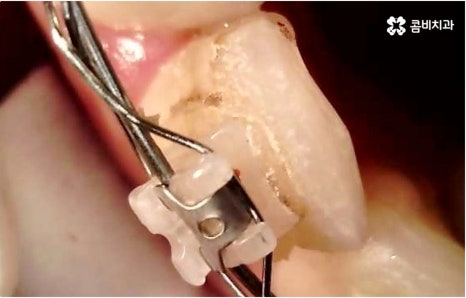

관리의 측면에서 교합이 맞지 않고 치열이 똑바르지 않으면 음식물 찌꺼기가 잘 끼고 잇몸이 붓기 쉽기 때문에 교정 치료가 필요할 수도 있습니다. 씹기가 어렵고 안면비대칭이나 턱관절 통증을 유발하는 등 심각한 부정교합의 경우 기능적으로도 필요하지만 약간 삐뚤어지거나 치아 사이가 벌어진 경우 심미적으로도 한 번쯤 교정 치료를 생각해 보셨을 텐데요, 가격이나 기간, 나이 등 여러 가지 부분이 신경쓰여서 막상 시작하기에 부감을 느끼고 계셨다면 먼저 명동치과 에 내원하셔서 자신에게 필요한 교정 치료가 어떤 것인지 알아보시면 좋을 거예요. 골격적인 원인이 크지 않고 정도가 심하지 않다면 환자분들의 상황에 따라 부분 교정으로 보다 짧고 간편하게 진행하는 경우도 있으니 3D CT 와 같이 정밀 검진 기계를 갖춘 치과에서 숙련된 의료진에게 검진 및 상담부터 받아보시길 권유드리고 있습니다.